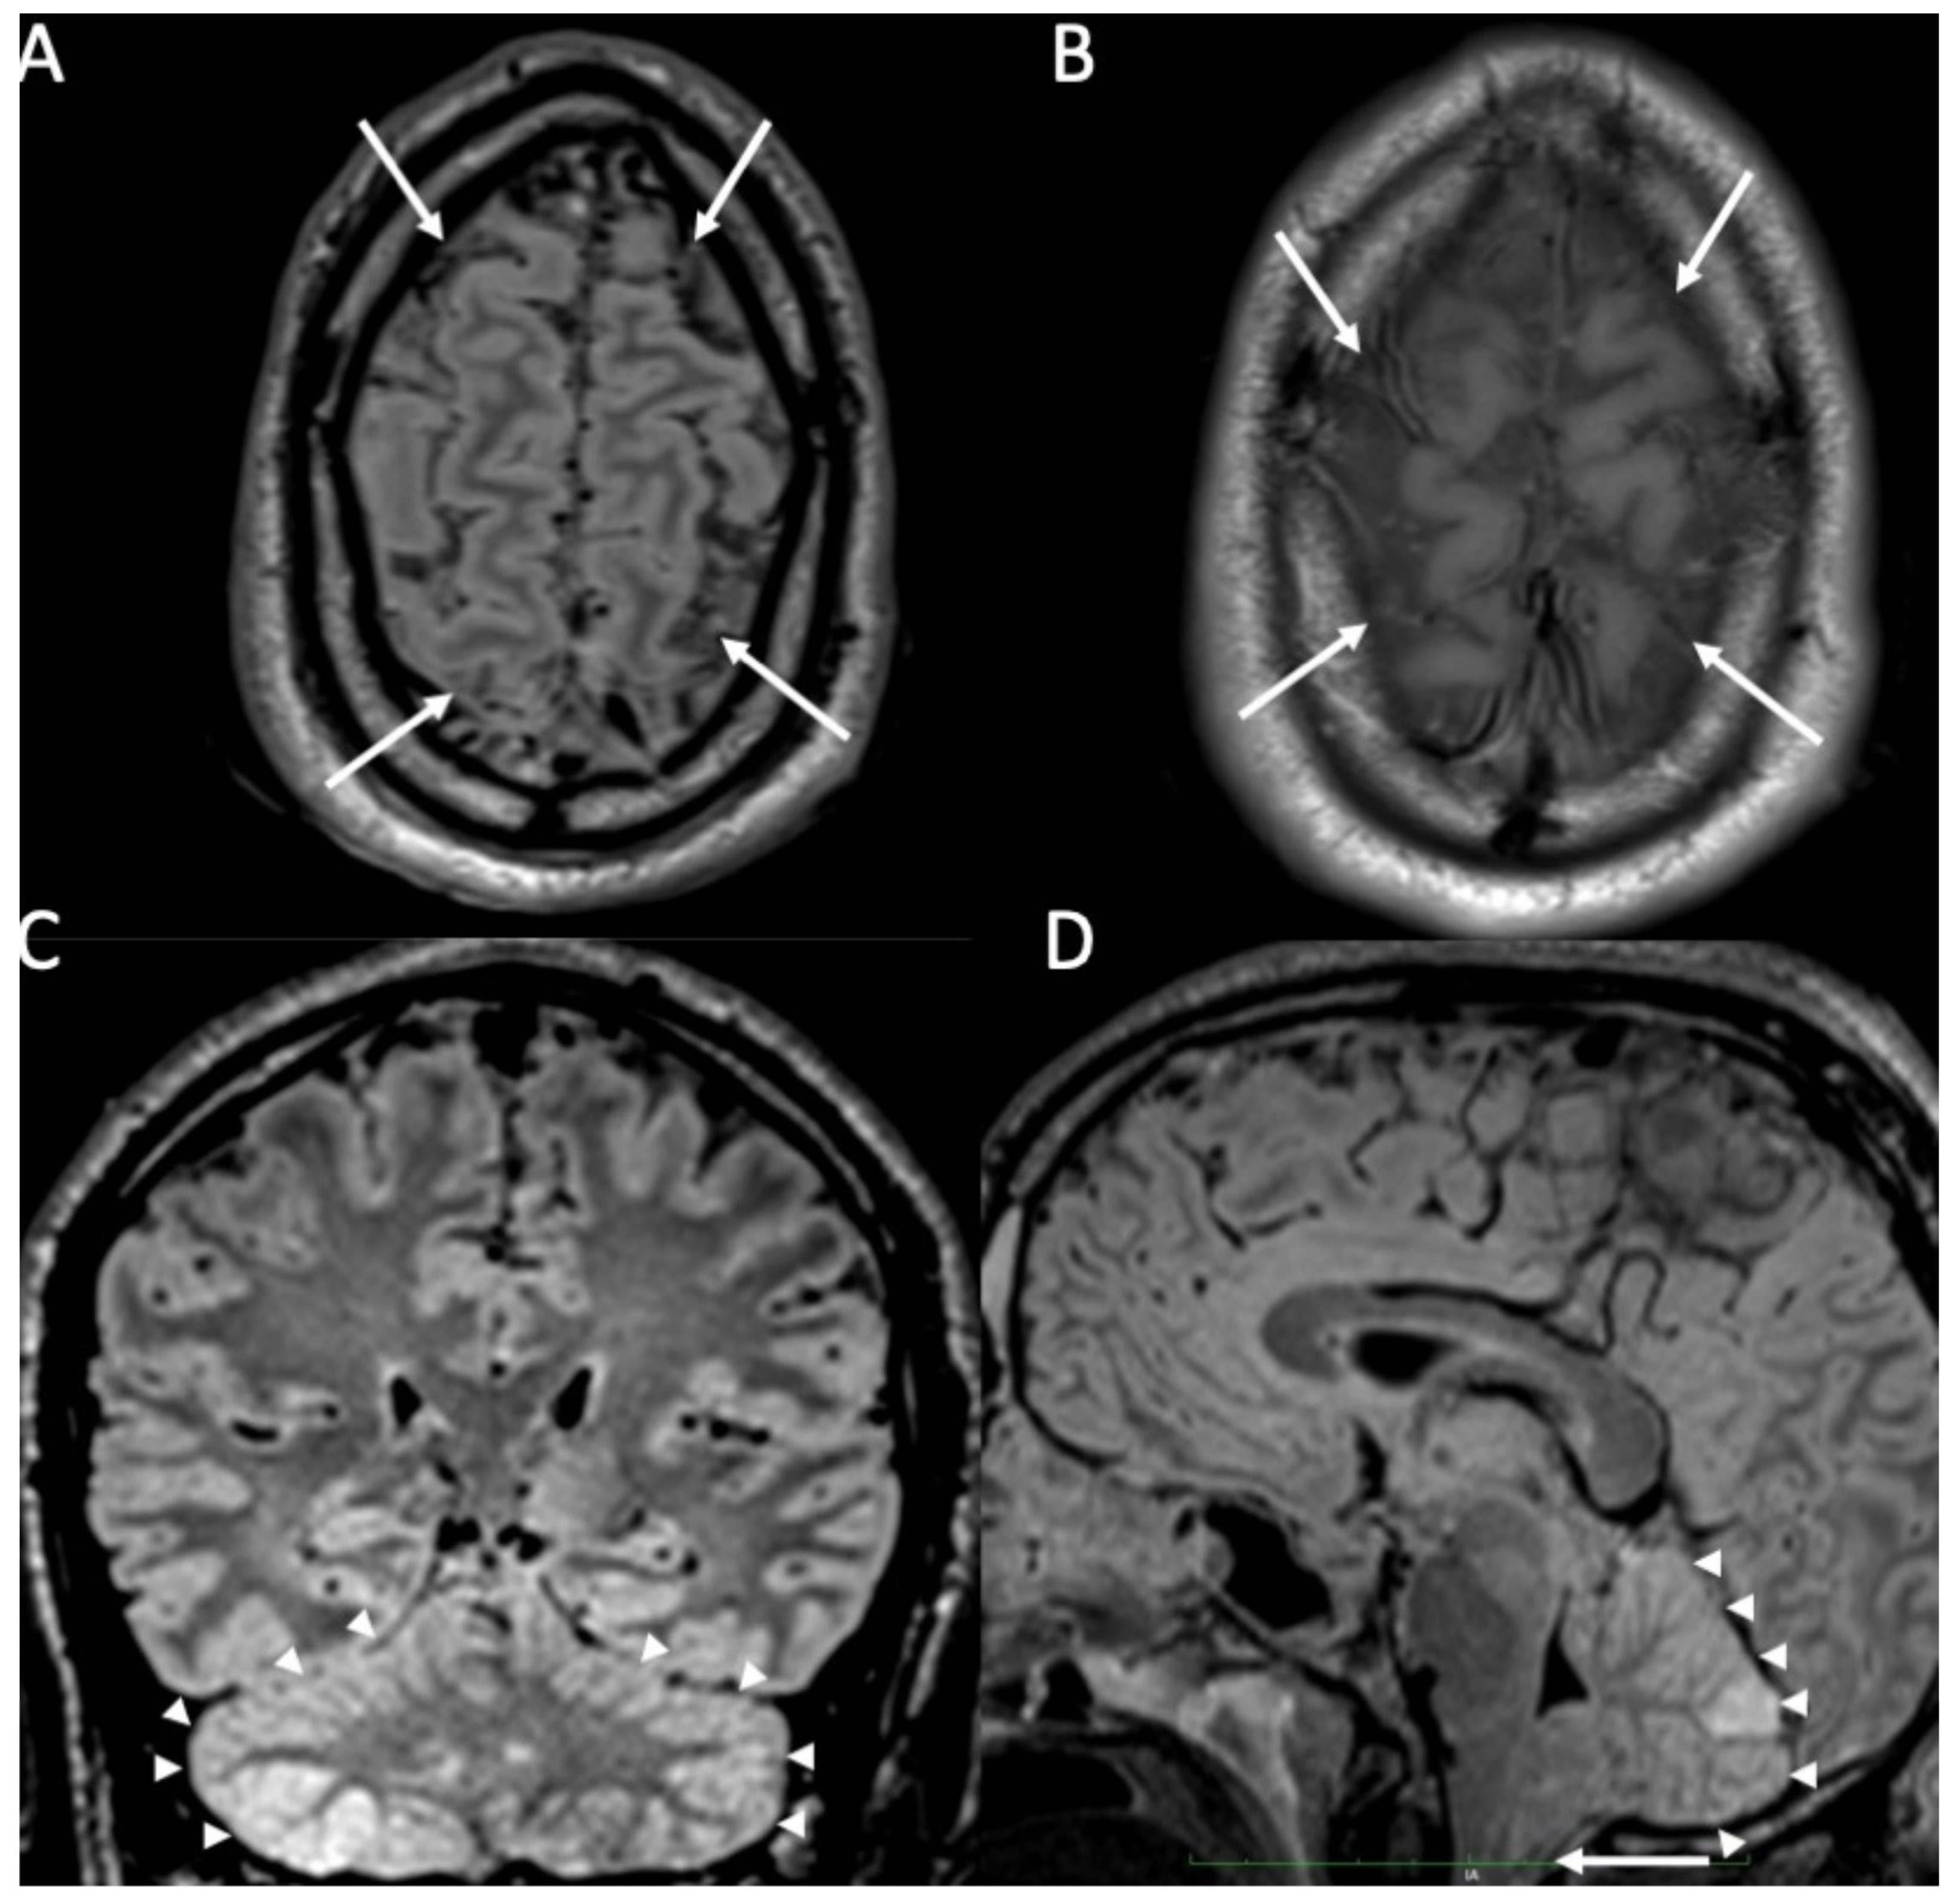

Figure 1.

Axial FLAIR (A), T1 (B), coronal (C), and sagittal FLAIR (D) show diffuse hyperintensity on FLAIR and T1 of the subarachnoid spaces mainly in the cerebral convexity (arrows in A,B) in a patient with Streptococcus Pneumoniae meningitis. Note also concomitant cerebellitis, which appears as diffuse cortical hyperintensity on FLAIR of the cerebellum (arrowheads in C,D), with herniation of the cerebellar tonsils (arrow in D).